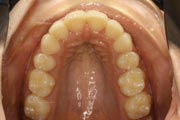

Crowding

After